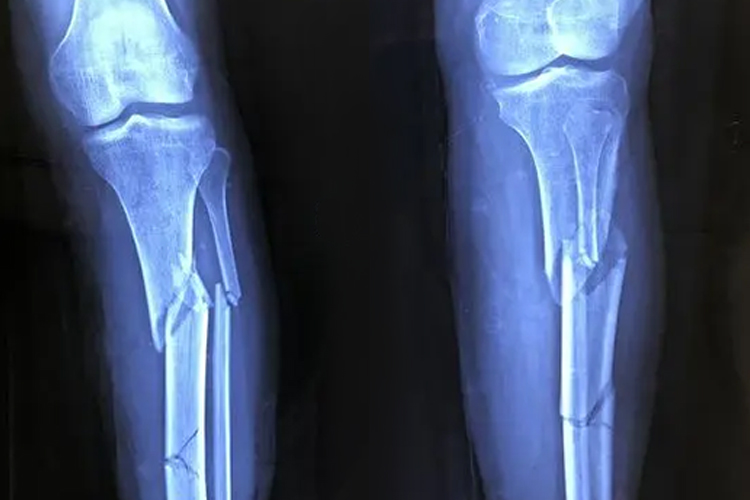

骨折x光主要可见骨折线,出现锐利而透明的裂隙,不全或细微骨折有时看不到明确的骨折线,会表现为骨皮质的皱褶、隆起、成角、凹陷,松质骨小梁的中断、紊乱、扭曲或嵌插。完全骨折时x光可见透光且明显的线状影,即骨折线。

骨裂情况较轻时,X光可能无法查出,明显时可见骨质连续性中断,出现淡且很细小的低密度影。